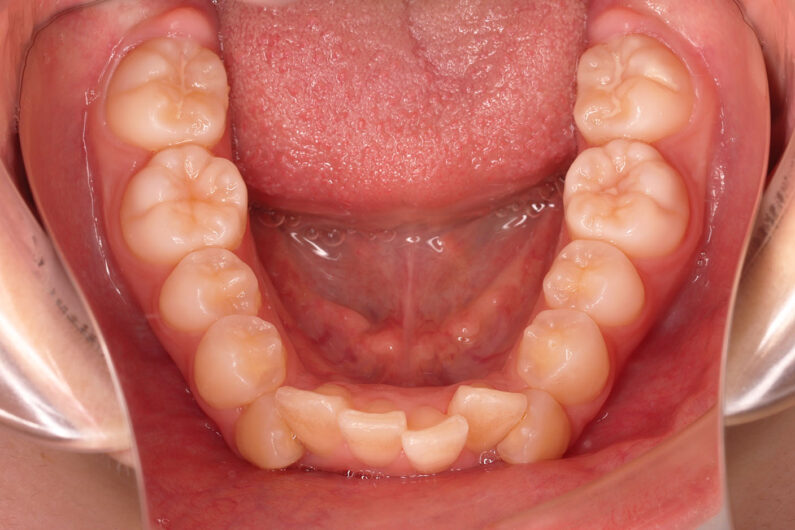

他院から紹介の患者さんです。 前歯、下の歯のガタツキをきれいにしたいということで治療を決断されました。

上顎前歯6mm、下顎前歯2.5mmの前突の状態で、口唇も前突しています。 小臼歯抜歯したスペースを使い、叢生(がたつき)と前突した前歯の後退を目標にしました。 この方も希望により、アンカースクリューは使用せず、通常の顎間ゴムで対処してもらいました。